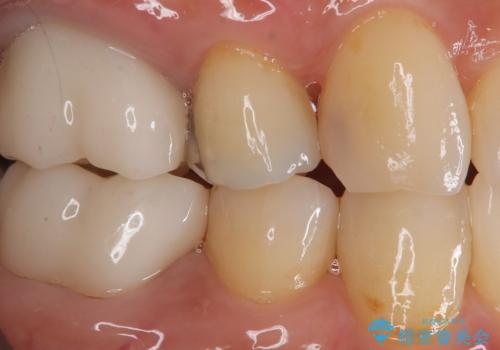

見た目も良く、満足していただきました。

セラミックインレーは、金属やプラスチックに比べ汚れが着きづらく、むし歯の再発リスクを減らすことができます。